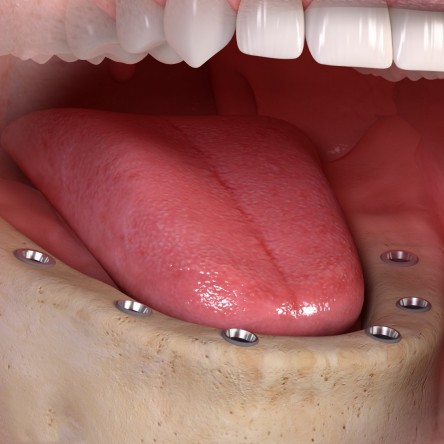

¿Qué es un implante?

Los implantes dentales son dispositivos que, insertados en el hueso, funcionan o actúan como una raíz artificial, soportando así la futura corona protética por medio de un aditamento intermedio conocido como pilar.

Es importante diferenciar entre cantidad y calidad de hueso. De la cantidad ósea dependerá el tipo de implante que se vaya a colocar, en términos de diámetro y longitud. Por su parte, la calidad ósea se perfila como factor clave al que estará supeditado la estabilidad de los implantes. La realización de un TAC (Tomografía Axial Computarizada) se presenta como el método radiodiagnóstico más fiable para la evaluación de los parámetros anteriormente descritos y llevar así una adecuada planificación de cada caso.

Consideraciones tras la colocación de los implantes

El concepto de osteointegración u oseointegración se define como la conexión directa, estructural y funcional entre el hueso y la superficie del implante durante las cargas funcionales o masticatorias. Este fenómeno dependerá de la capacidad de cicatrización, reparación y remodelado de los tejidos, tanto del hueso como de la encía. Así, para poder establecer un pronóstico predecible, la manipulación y cuidado meticulosos de los mismos resulta clave para poder hablar de éxito clínico.

Durante la fase de osteointegración existen dos etapas claramente diferenciadas:

Estabilidad primaria. Es la que se establece entre el hueso y el implante tras la colocación del mismo y se prolonga durante 2 semanas aproximadamente.

Estabilidad secundaria. Es la que se establece a partir de la 2ª ó 3ª semana tras la colocación del implante al formarse nuevo hueso durante el período de reparación ósea.

FASE CRÍTICA. Al tiempo que la estabilidad primaria se pierde y se va ganando estabilidad secundaria, existe un período crítico en el cual la estabilidad implantaria se va a ver notablemente reducida, poniendo en riesgo el proceso de osteointegración. Por lo tanto, es de obligado cumplimiento respetar los tiempos biológicos de cicatrización de los tejidos antes de llevar a cabo cualquier tipo de restauración protética, esto es, la colocación de la corona sobre el implante.